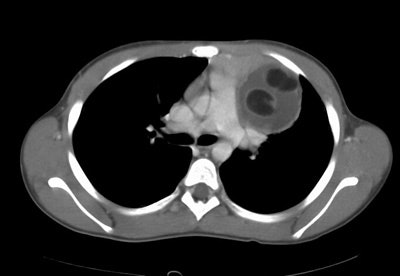

The case below is of a 9 year old girl that presented with an abnormal CXR. A large anterior mediastinal mass is demonstrated on the CT with macroscopic foci of fat attenuation. (Click image to enlarge)